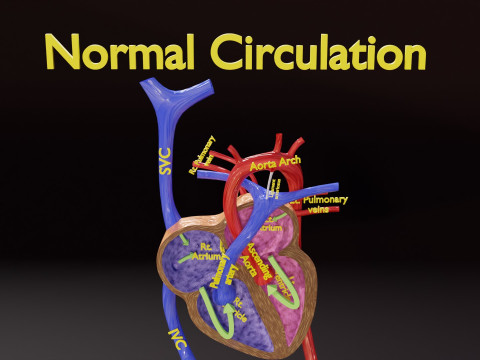

The model meshes include adult circulation versus circulation in Tetralogy of Fallot (TAF), arrow labels and text labels. The blood flow in a patient with Tetralogy of Fallot is outlined in this model. To contrast it to normal blood circulation a separate model of normal circulation is included. The Tetralogy of Fallot (OVER RIDING OF AORTA, PUL STENOSIS, VENTRICULAR SEPTAL DEFECT, RIGHT VENTRICULAR HYPERTROPHY), fossa, ligament teres , venosus, and arteriosus are duly depicted with proper labelling and blood flow directional arrows. Excellent model for teaching, demonstration and knowlegde of human body. The models include both procedural and image textures blend files separately. The texture file include diffuse, roughness and normal png and jpeg based on non overlapping UV maps.